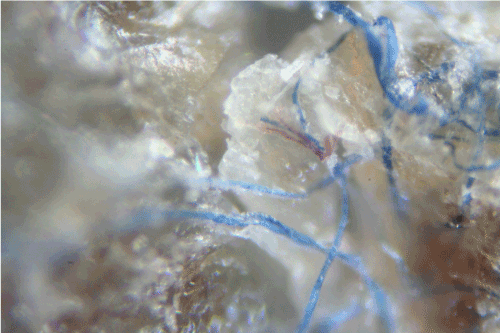

Some samples revealed raised unidentified papules protruding from dried epithelial tissue that might be abnormal hair follicles. Long isolated colored filaments, filament fragments, balls, and clumps of fibers (red, blue, black and green) were also observed, but were not attached to or growing from epithelial tissue. Many of these colored filaments had bulb-like ends (50 μm diameter) that looked very much like those found in hair follicles (Figure 2E).

Figure 2E: Blue filament with bulb-like ends (50 μm diameter) similar to a hair follicle from Case 1 (100x magnification).

Case 2: Microscopic examination of scab material revealed scab detritus imbedded with long filaments of various colors (Figures 3A- 3D). Hyaline, red, blue, and light purple fibers were observed (10-40 μm diameter) (Figure 3A, Figure 3B). One sample revealed fibers tangled around a hair and these fibers may have been associated with the hair follicle (Figure 3C). Smaller, pale purple fibers (10 μm diameter) appeared to form a mesh around the follicle. Some samples revealed fibers that lay beneath or penetrated dermal tissue Figure 3D.

Figure 3A: Red and blue fibers in skin samples from Case 2 (100x magnification).

Figure 3B: Red and blue fibers embedded in skin from Case 2 (100x magnification).

Figure 3C: Fibers tangled around a hair (larger black shaft to right of figure) in Case 2 (100x magnification).

Figure 3D: Fibers penetrating dermal tissue from Case 2 (100x magnification).